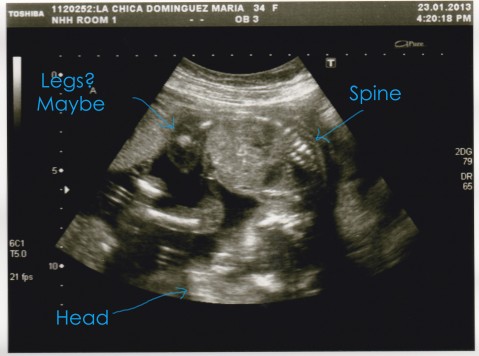

Here are the pictures that we got yesterday:

This is Dixie (bottom one – and a very awkward picture, sorry!)